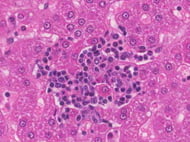

Bone marrow is recognized to be the chief and the most accessible stem cell source recently. The bone marrow niche is responsible for holding the heterogeneous population of mesenchymal stromal cells, along with cells of hematopoietic origin; in order to offer physical support to their hematopoietic counterparts and also differentiate into different progenitors to guarantee a functional remodeling of the BM niche. More importantly, these stromal cells are also involved in the direct regulation of hematopoietic homeostasis in a paracrine manner through the secretion of different soluble factors. Due to these specific properties, these cells have high demand currently for multiple in vivo, in vitro, and ex vivo assays. Kosheeka is providing cells with the optimum in-house quality control procedures.The cells are tested for morphological analysis, growth rate potential, adherence rate potential, and surface characterization potential for a comprehensive panel of markers. The cell sources are also assessed for infectious panel markers like HIV-1/2, HBV, HCV and HTLV 1/2, etc.

Mesenchymal stem cells, also commonly known as mesenchymal stromal cells obtained from bone marrow are multipotent cells with the ability to differentiate into cells of various mesenchyme origins....